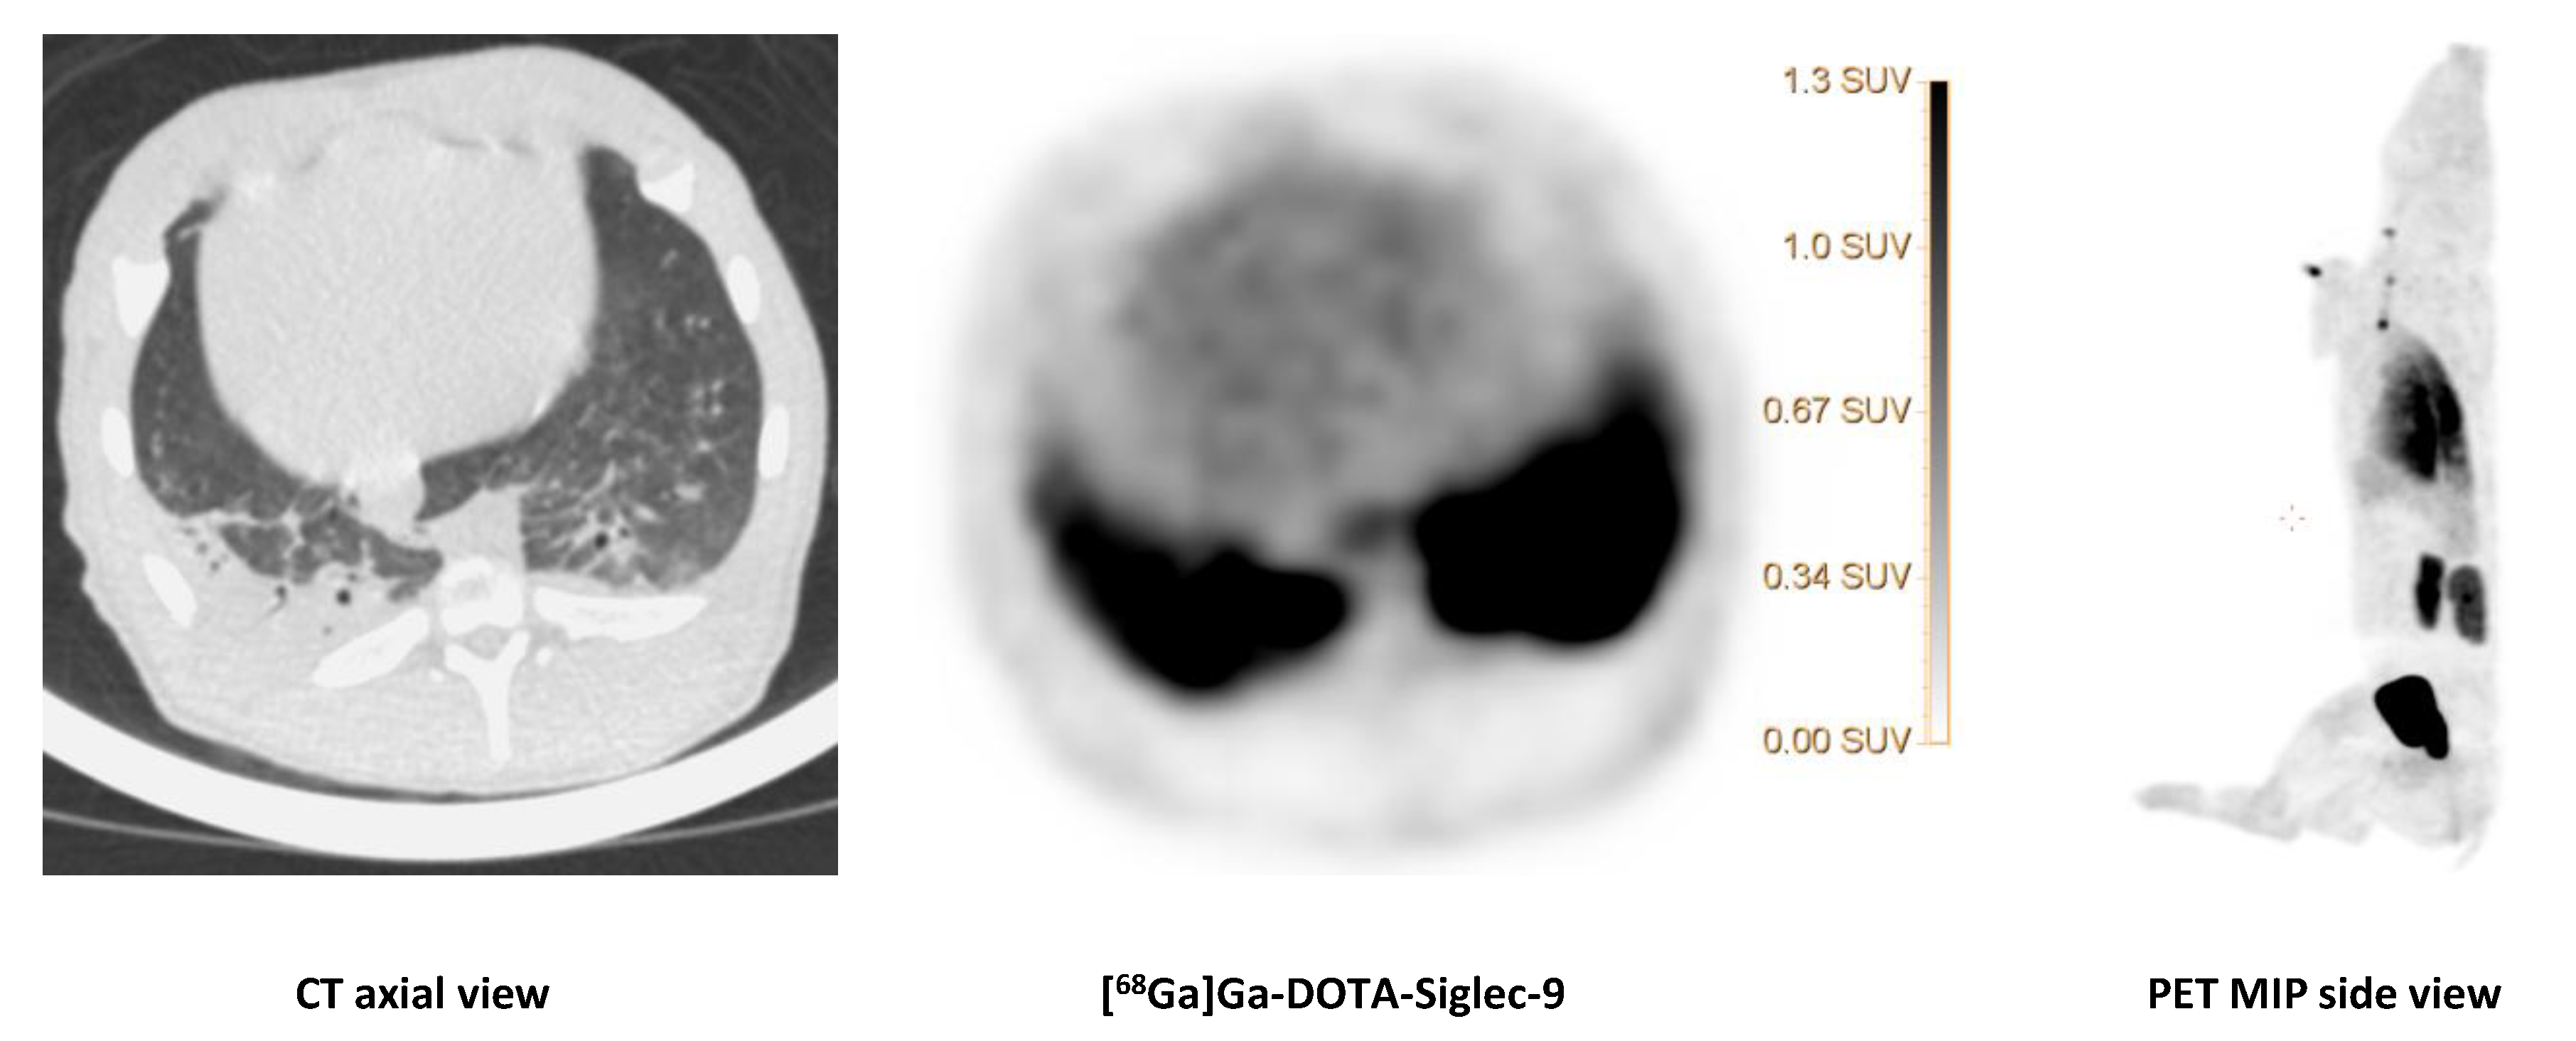

The CT image (axial view) of the dorsocaudal parts of the lungs of pig 1 showed signs of infection and partial atelectasis (arrow) and the corresponding [68Ga]Ga-DOTA-Siglec-9 uptake in the corresponding anatomical area. Axial views of CT and PET and a MIP (side view) of [68Ga]Ga-DOTA-Siglec-9 distribution in the pig’s body. The SUV scale bar is shown in the axial PET image.

Figure 7. [68Ga]Ga-DOTA-Siglec-9 uptake in the lungs.